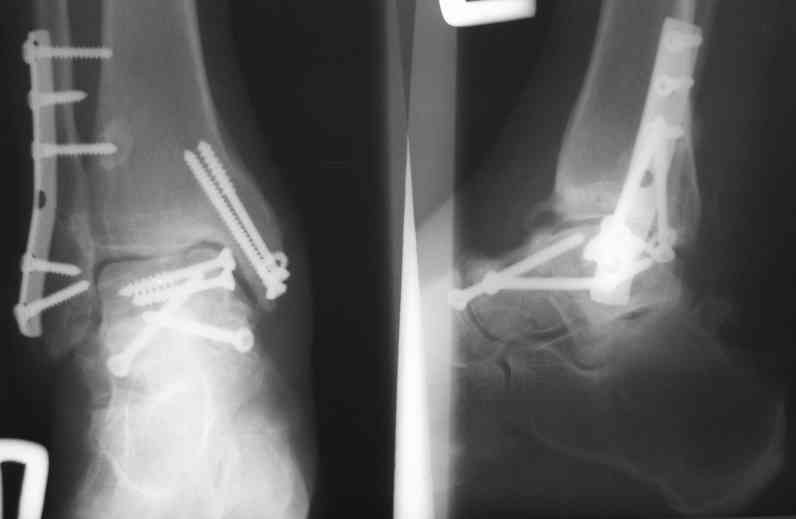

Решили не связываться с остеосинтезом, а сделать сразу берцово-пяточный блок. Снимки в приложении.

По завершении удлинения, наверно, заштифтуем.

Комментарии/критика приветствуются.